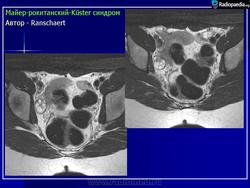

Синдром Mayer-Rokitansky-Küster.

Майера — Рокитанского — Кюстера с. — наследственные аномалии развития матки (возможно, аутосомно-доминантное наследование) : в анамнезе первичная аменорея, стерильность; нормальное развитие вторичных половых признаков и нормальное появление менструаций. Иногда викарирующие кровотечения из мочевого пузыря, прямой кишки, полости рта или носа. Наружные гениталии: общая гипоплазия, часто дорсальное расположение и воронкообразное расширение отверстий мочеиспускательного канала. Внутренние гениталии — влагалище почти полностью отсутствует; матка обычно разделена на 2 части, без полости, эндометрий отсутствует; яичники расположены относительно высоко, яйцевод гипопластический, но с просветом. Вторичные Половые признаки; нормальный женский внешний облик, развитие молочных желез нормальное, оволосение типично для женского пола. Нормальное поло­вое влечение. Овариальная функция: нормальная базальная температура, нормальное содержание прегнандиола и эстрогенов в моче. Нередко сочетается с аномалиями почек и мочевых путей; иногда наблюдаются врожденная аневризма аорты, аномалии мезентерия, сакрализация Vпоясничного позвонка, гипоплазия XIIребра.